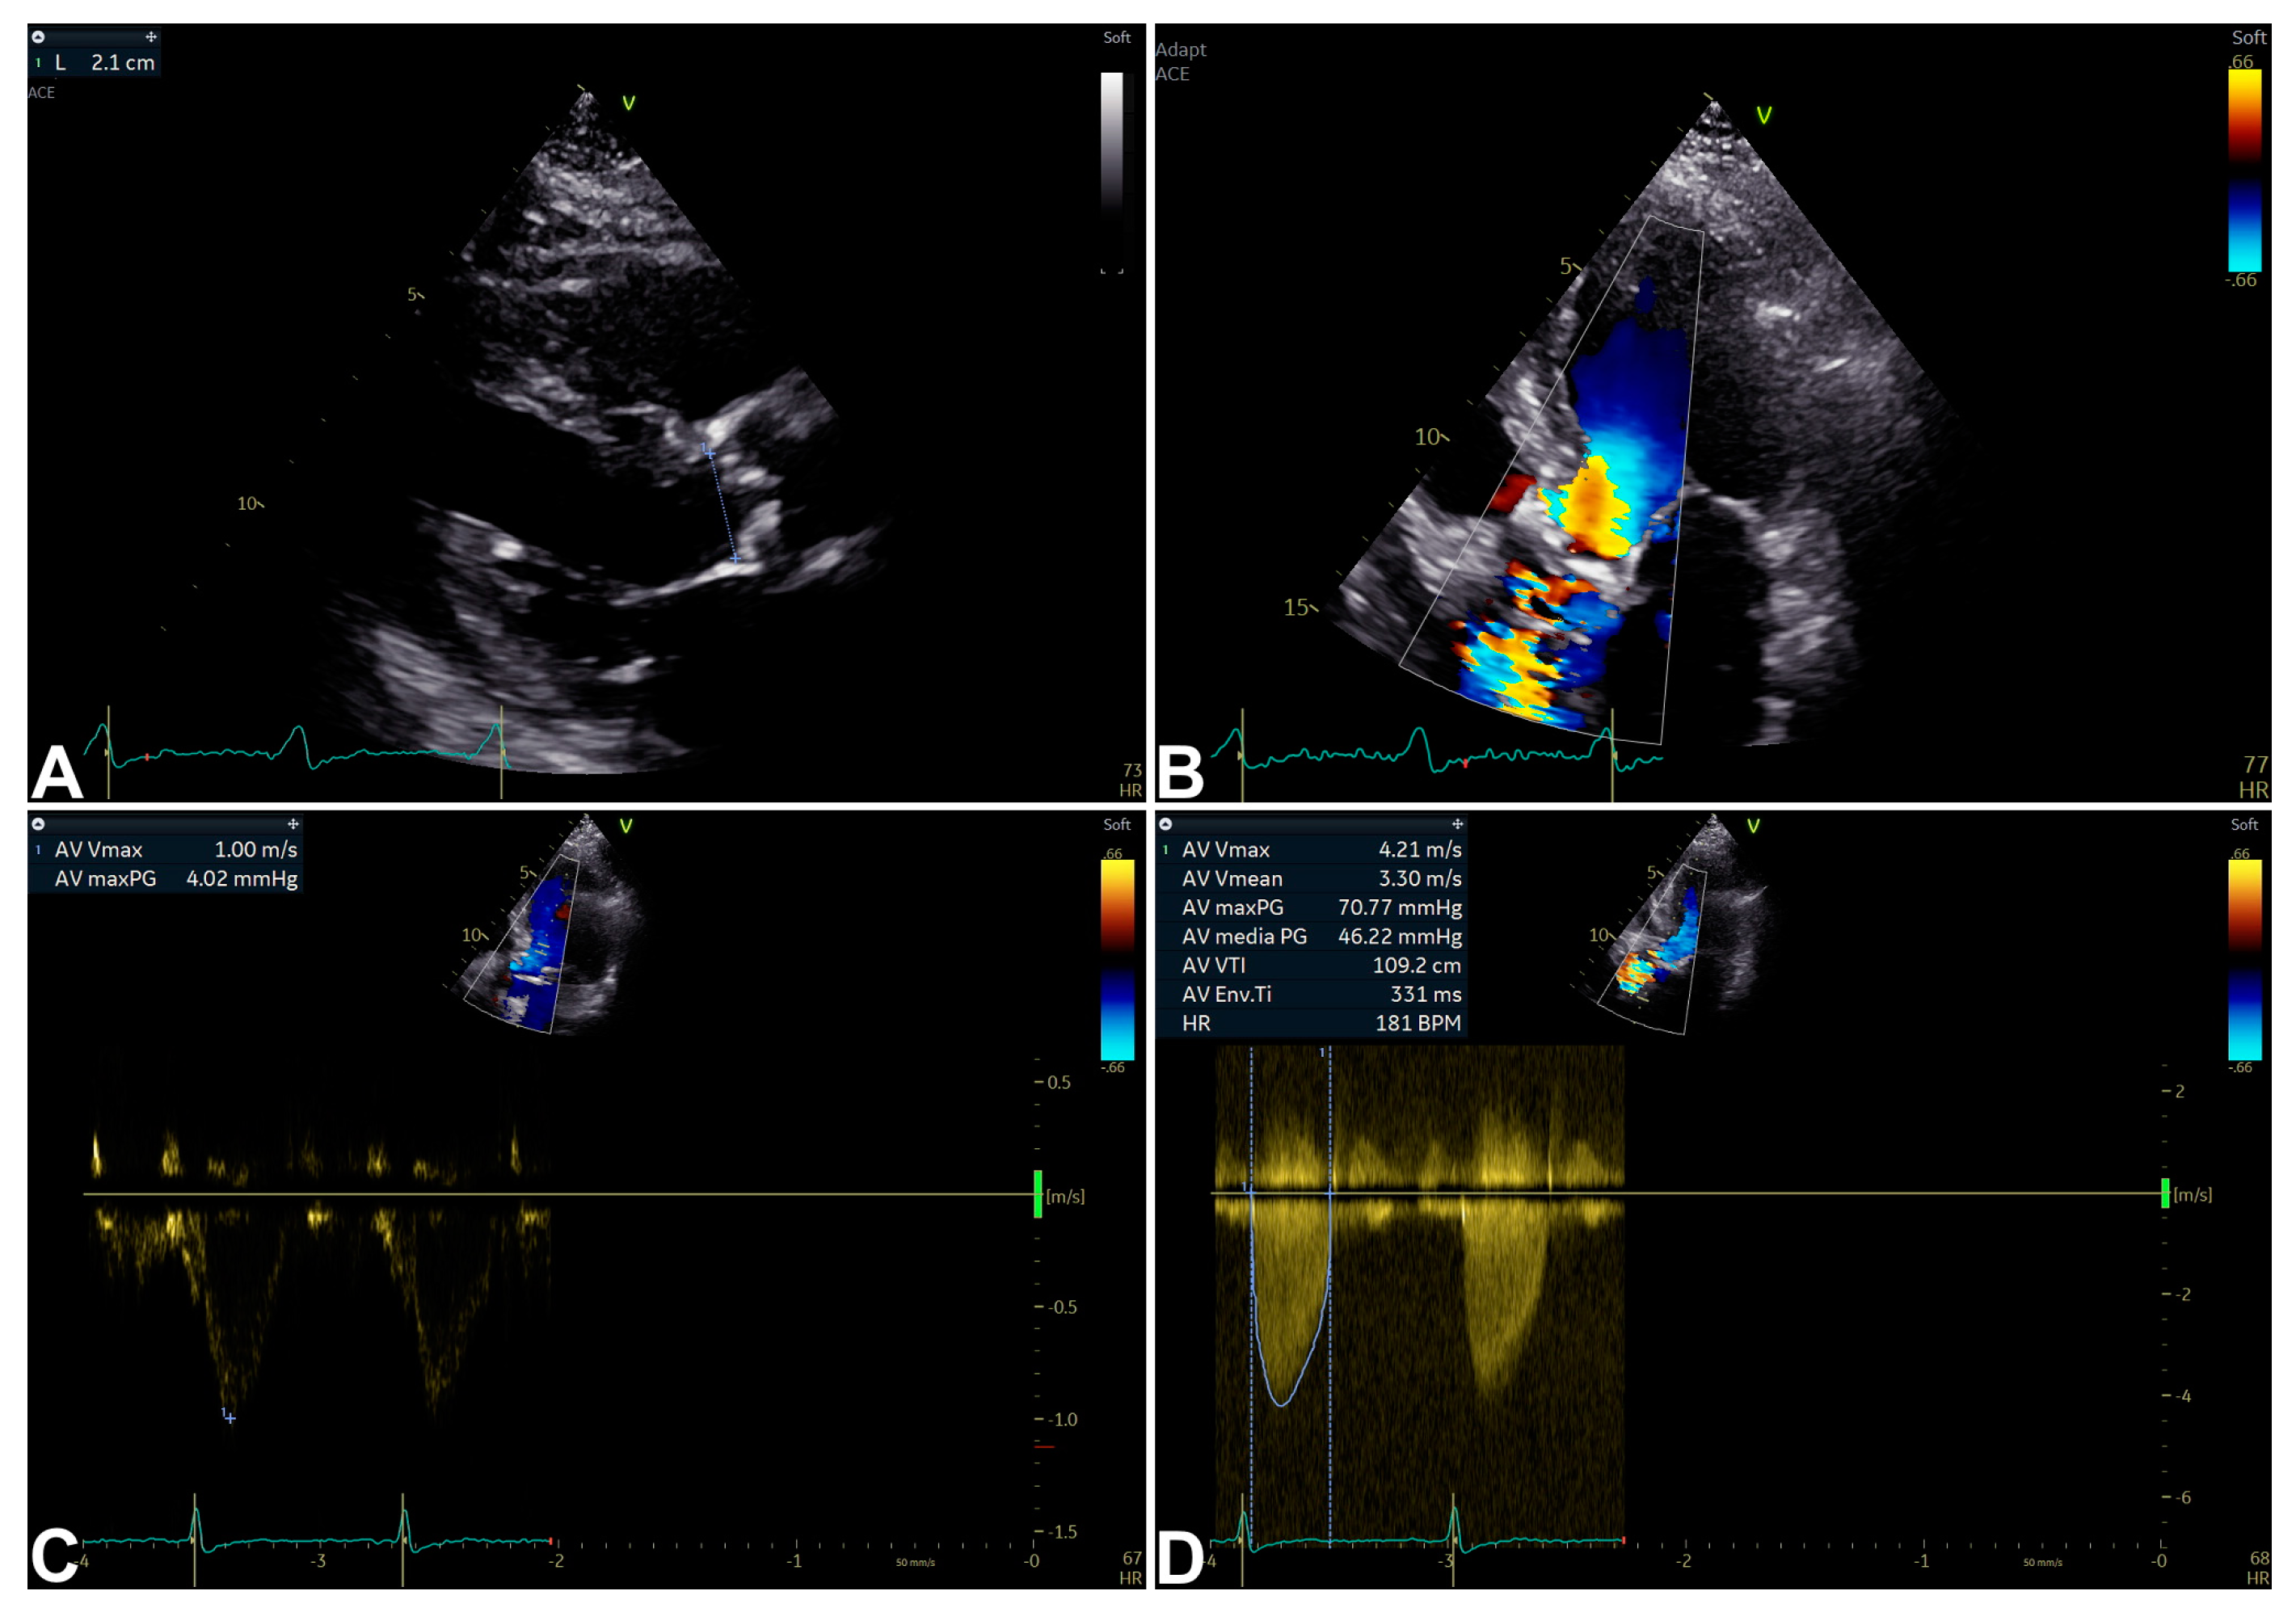

3. Echocardiography for Isolated Severe Aortic Stenosis Assessment and Characterization

| Peak velocity (m/s) | ≤2.5 | 2.6–2.9 | 3.0–4.0 | ≥4 | - Direct measurement. - Strong predictor of clinical outcome. | - Flow-related. - US beam parallel alignment-related. |

| Mean gradient (mmHg) | None | <20 | 20–40 | ≥40 | - Units comparable to invasive measurements. | - Flow-related. - US beam parallel alignment-related. |

| AVA (cm2) | None | >1.5 | 1.0–1.5 | <1.0 | - Effective orifice area measurement. - Frequently feasible. - Relatively flow-related. | Measurement error more likely. |

| iAVA (cm2/m2) | None | >0.85 | 0.60–0.85 | <0.60 | - Effective orifice area measurement. - Frequently feasible. - Relatively flow-related. - More accurate than AVA. | Measurement error more likely. |

| Velocity ratio | None | >0.50 | 0.25–0.50 | <0.25 | - Less variability than AVA (Doppler-only required). | - Limited longitudinal data. - Ignores LVOT size variability. |